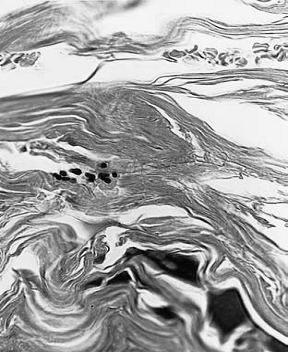

Malassezia pachydermatisMalassezia pachydermatis pod svetlosnim mikroskopomUzorkovanje materijala za citološki pregled vrši se skarifikacijom kože, uzimanjem briseva celofanskom trakom ili štapićima za bris. Ova metoda omogućava direktan uvid u prisustvo ćelija Malassezia pachydermatis u materijalu uzetom jednom od navedenih metoda. Od navedenih metoda uzorkovanja najčešće se koristi celofanski bris, dok uzimanje uzoraka štapićima za bris se koristi kod uzimanja uzoraka kod otitis externa. U materijalu uzetom za citološki pregled uočavaju se okrugle ili ovalne ćelije veličine 3 – 5μm.

Slike br. 7 i 8, Prikaz ćelija Malassezia pachydermatis pod svetlosnim mikroskopom